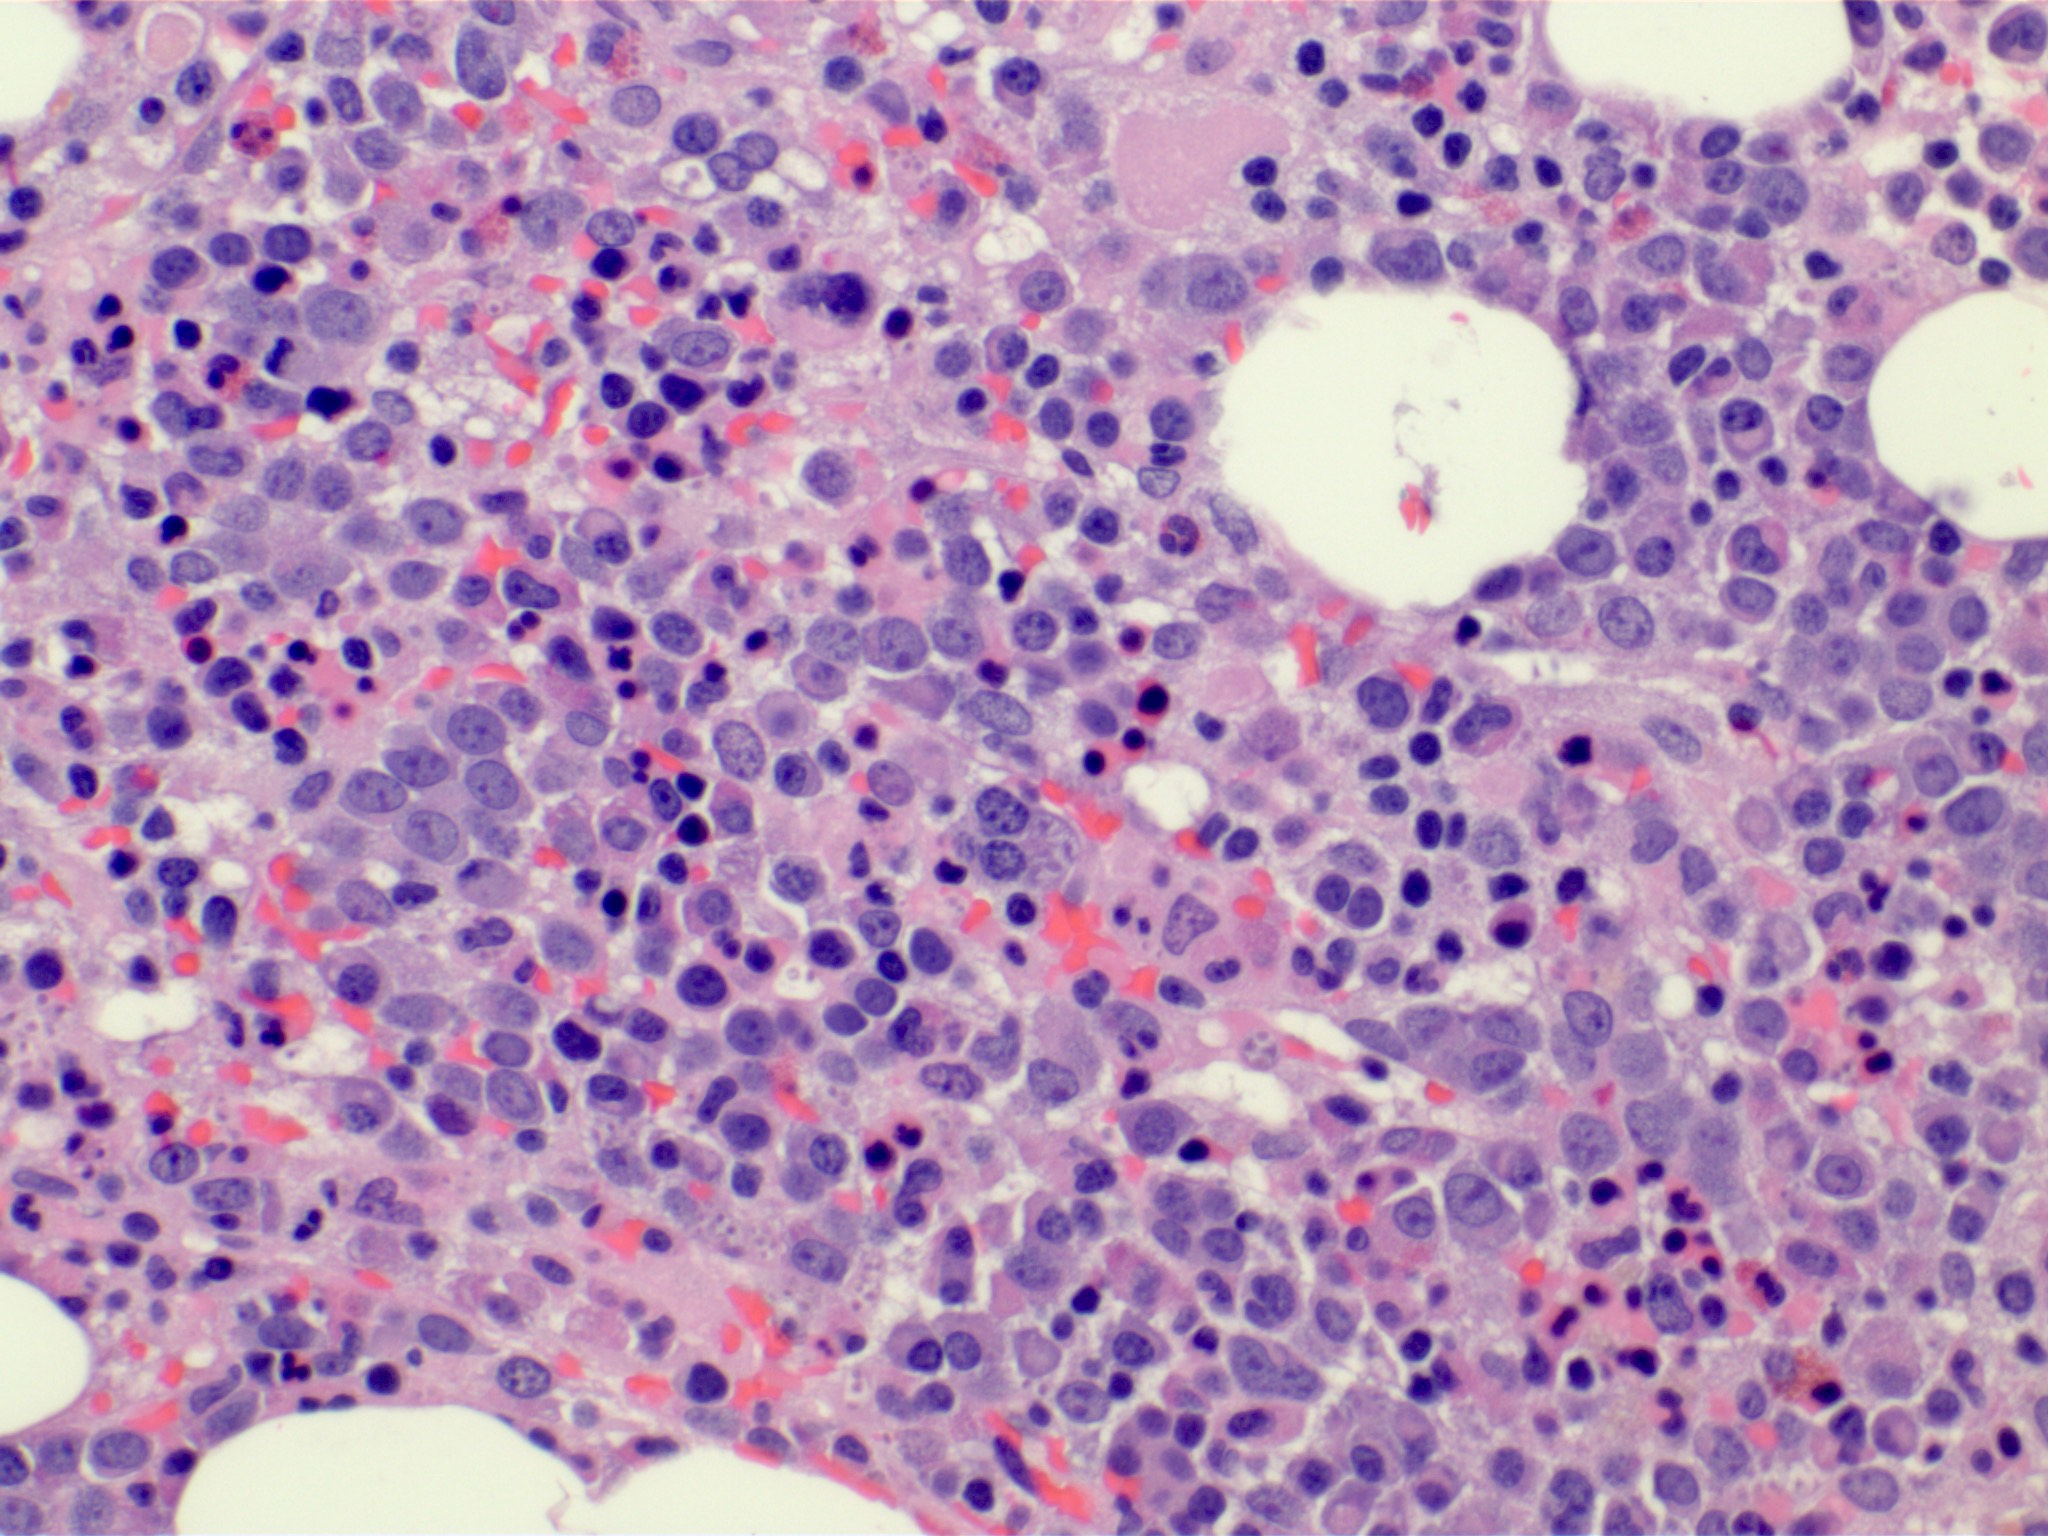

Microscopic (histologic) description

- Bone marrow (Front Oncol 2021;11:778741)

- Dysplasia is seen in at least one hematopoietic lineage

- Percentage of blasts in peripheral blood and bone marrow must be < 20%

- Typically few blasts are seen

- Include promonocytes as blast equivalents

- Increased megakaryocytes with variable clustering

- Often myelodysplasia-like with small size and nuclear hypolobation

Microscopic (histologic) images